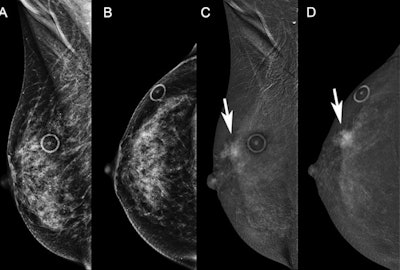

Mass enhancement on recombined images using contrast-enhanced mammography (CEM) is associated with malignancy, especially when linked to low-energy findings, a study published July 12 in Radiology found.

Out of these, 190 CEM studies showed enhancement findings. The researchers found that enhancing lesions were more likely to be malignant when associated with low-energy findings (26% vs. 59%) (p = 0.001).

The team also found that among enhancement types, mass enhancement composed 71% (99 of 140) of all malignancies with a PPV of 63% when linked to low-energy findings. Foci, non-mass enhancement, and mass enhancement without low-energy findings had PPVs of 6%, 24%, and 38%, respectively. Non-mass enhancement was also more likely to be benign overall (PPV, 43%), but the likelihood of malignancy was higher (PPV = 82%) when linked to calcifications.